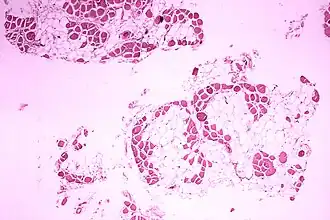

| Imagem microscópica do músculo da perna (gémeo) de um indivíduo com distrofia muscular de Duchenne. A secção transversal do tecido muscular mostra uma substituição extensa das fibras musculares por células adiposas. | |